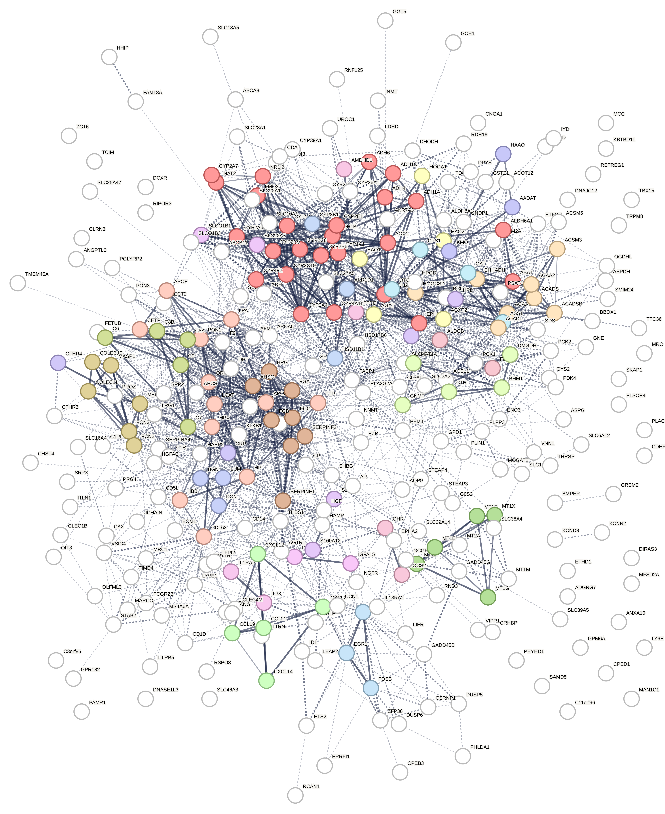

The intersection of DEGs from the TCGA and GEO databases revealed 324 co- upregulated genes (Figure 3A) and 321 co-downregulated genes (Figure 3B). These common upregulated and downregulated genes were further analyzed for their interaction networks using the STRING database, revealing widespread gene interactions. The DBSCAN clustering algorithm identified 12 clusters for upregulated genes and 24 clusters for downregulated genes. The most central cluster in the upregulated genes was designated as cluster 1, serving as a hub gene, while the most central clusters in the downregulated genes were clusters 1 and 2, which were also considered hub genes. Figures 4 and 5 illustrate the clustering of interaction proteins and their network distributions. A total of 94 hub genes showed increased expression, while 37 showed decreased expression.